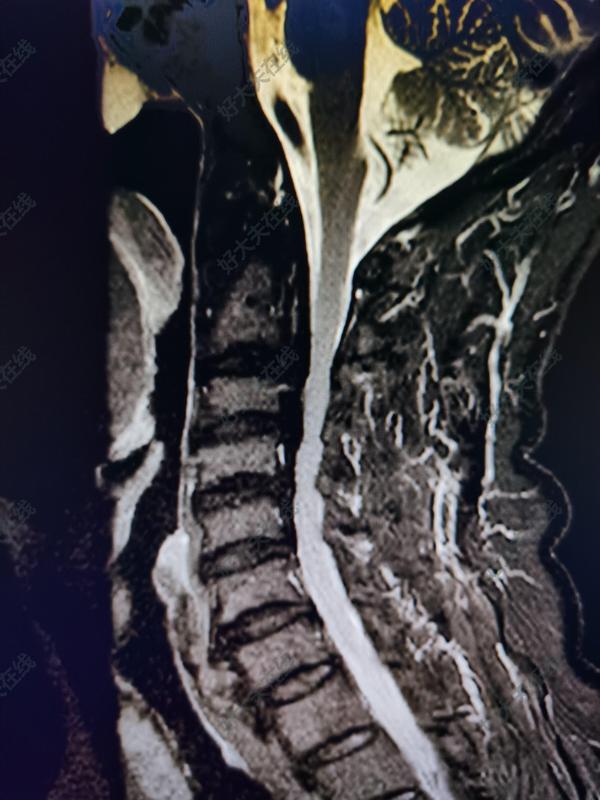

治療前 患者肢體麻木無力,走路不穩(wěn),有踩棉花樣感覺,核磁提示頸椎多節(jié)段椎間盤脫出、后縱韌帶增厚鈣化、黃韌帶肥厚,引起椎管狹窄、脊髓受壓。 治療中 椎頸椎病手術(shù):椎管狹窄單開門擴大成形術(shù)。改良了手術(shù)方法:經(jīng)過頸椎后方手術(shù)再不用切斷肌肉,手術(shù)中出血僅50毫升左右,術(shù)后將肌肉和骨質(zhì)恢復(fù)原來結(jié)構(gòu),進一步體現(xiàn)了“微創(chuàng)”理念,避免了以前容易出現(xiàn)的很多并發(fā)癥。 隨著內(nèi)固定材料的降價,頸椎椎管狹窄“單開門”手術(shù)的住院費用由原來的10萬元左右將到了4萬元左右。 治療后 治療后即刻 四肢麻木無力感明顯減輕,走路不穩(wěn)癥狀改善,踩棉花感消失